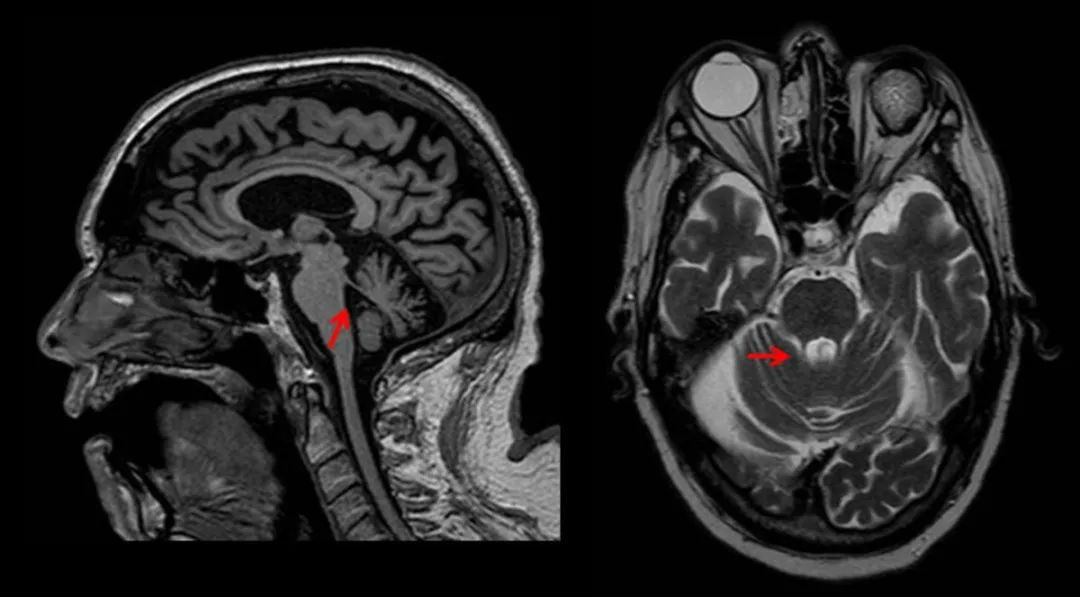

MSA-C 型的 MR 常出现:橄榄、桥脑、小脑中脚和小脑的萎缩,横轴面上桥脑 T2WI 交叉样高信号,即所谓的「十字征」,是诊断 MSA-C 的较特征性的表现。「十字征」的病理学基础为桥脑核及其发出的通过小脑中脚到达小脑的纤维 (桥横纤维) 变性和神经胶质增生,T2WI 信号增高。有学者认为,先出现「垂线征」(需要仔细观察),后出现「十字征」。但「十字征」并非 MSA-C 型所特有,其他疾病比如遗传性小脑共济失调也可出现。

橄榄、桥脑、小脑中脚和小脑的萎缩,出现「十字征」

PSP 的 MR 常出现:特征是中脑和被盖萎缩;在矢状位中,中脑被盖萎缩形似「蜂鸟」;在轴位中,中脑萎缩,顶盖和大脑脚保留形似「米老鼠」。

PSP中小脑上脚萎缩